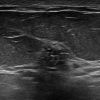

Ung thư vú

Ung thư vú - Ảnh 5

» Thông tin: Nữ giới – 42 tuổi.

» Lâm sàng: Kiểm tra sức khỏe.